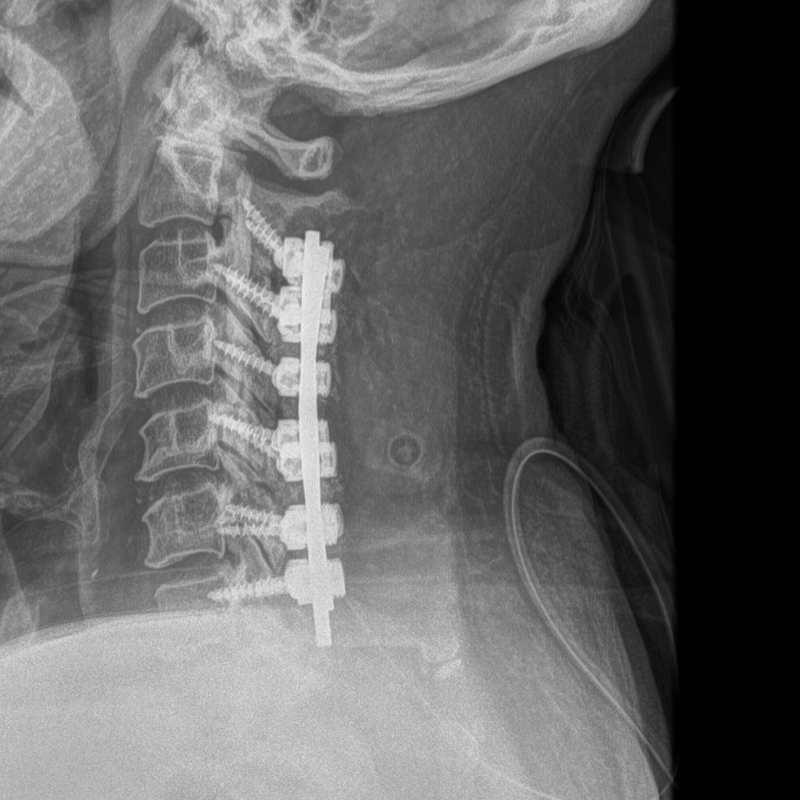

Given the severity of spinal canal stenosis and associated spinal cord compression, surgical intervention was pursued. Treatment for OPLL in cases such as this typically focuses on decompressing the spinal cord and stabilizing the cervical spine to prevent further neurologic decline. In this case, a postoperative X-ray demonstrates the implanted hardware used to provide spinal stability following decompression.

Figure G (Right): Post-op X-ray, showing implanted hardware.